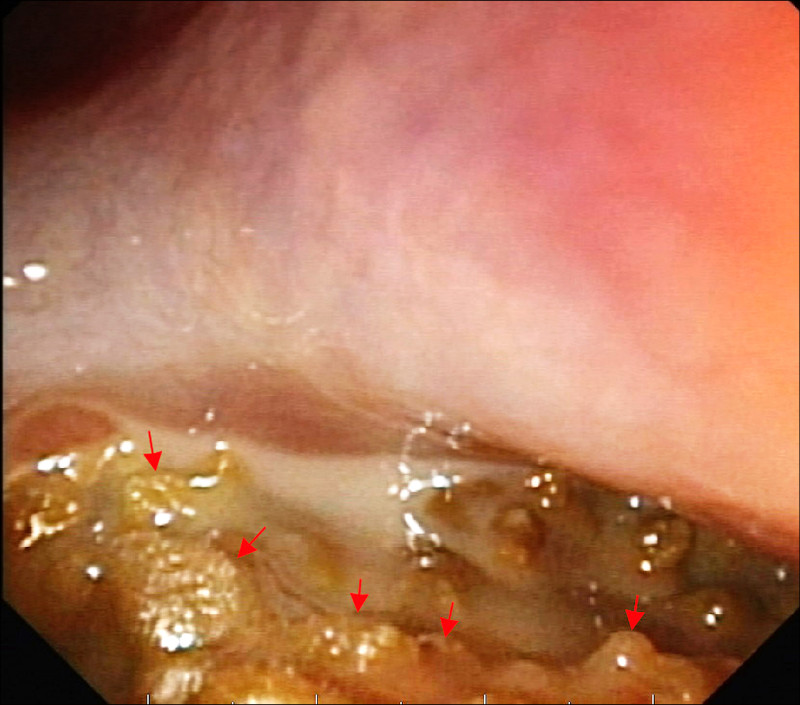

56歲的林小姐半年來飽受鼻塞、咳嗽有痰偶爾帶血絲,服用多輪抗生素治療未改善,經轉介前來就醫,內視鏡檢查確認是鼻竇炎問題,結合電腦斷層檢查發現,引起鼻竇炎的罪魁禍首不是細菌,而是感染了黴菌!(圖1)黴菌在她的鼻竇裡堆積成黏土狀(圖2),即使鼻沖洗也難以清除,須手術打開鼻竇、完整移除黴菌塊,手術後她不需使用抗黴菌藥物即可順利康復,也終於放下心中的大石。

黴菌球不是腫瘤,不會侵蝕鼻竇,但會在鼻竇中逐漸堆積、乾燥凝結,形成一團像黏土般的硬塊,無法自行排出。黴菌球內常有鈣化,影像學檢查上會呈現亮白如石頭般的特徵(圖3)。

治療方面,黴菌球因常伴隨細菌感染,單靠抗生素可能稍有改善但無法根治;抗黴菌藥物也無法深入團塊內部,鼻沖洗更無法徹底清除,所以,最有效的治療方式是以微創內視鏡手術(ESS)打開鼻竇開口,徹底移除黴菌塊,手術傷口小、恢復快,復發率低。